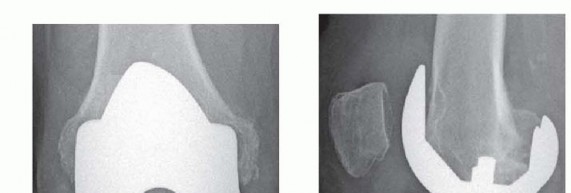

P ITFALLS Examine the preoperative lateral radiograph carefully for patella baja as these patients are poor c…